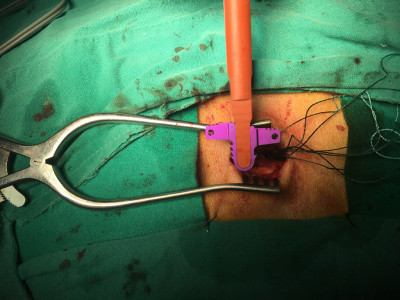

Cirugía de columna de mínima invasión

Envíado por Dr. Hugo Enrique Castro Cordero